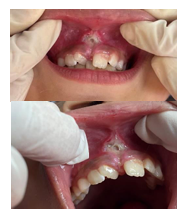

Figura 3: A, B, C, D, E, F – Transcirúrgico (incisão, descolamento de fibras, fotovaporização)

Iniciou-se a cirurgia com uma prévia antissepsia extraoral realizada com clorexidina aquosa 2% e intraoral com antisséptico bucal 0,12% e aplicou-se o anestésico tópico Benzotop 20% no local. Após 2 minutos, infiltrou-se, bilateralmente, o anestésico local Cloridrato de Lidocaína 2% com Epinefrina 1:100.000 em fundo de vestíbulo dos dentes 11, 12, 21 e 22, e bloqueio de nervo nasopalatino. Depois de 5 minutos, a incisão, iniciada na base do freio e depois na parte superior entre a base desse triângulo. foi realizada com laser de diodo de alta potência (TW SURGICAL – MMO), modo contínuo, comprimento de onda de 808 nm e potência de 4,5W. Foi removida a mucosa do frênulo e o tecido profundo constituído de fibras conjuntivas e musculares. Não foi necessária síntese, pois uma das vantagens do laser cirúrgico de alta potência é a hemostasia instantânea.